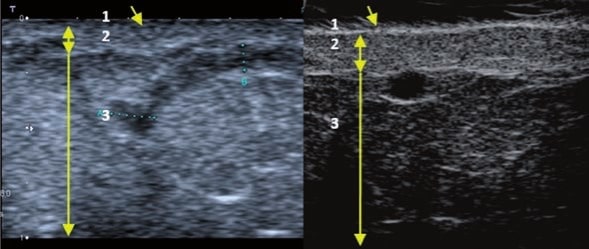

La sonographie Doppler permet l’imagerie des gros vaisseaux et des perforantes qui sont généralement situés dans les couches plus profondes du tissu sous-cutané (fig. 1). Malheureusement, la sonographie conventionnelle n’est pas capable d’imager les vaisseaux plus petits. Afin de visualiser les vaisseaux plus petits situés près de la surface de l’épiderme et dans la couche supérieure du tissu sous-cutané, l’EHF est utilisée (fig. 1). Grâce à l’utilisation de transducteurs dont les fréquences sont supérieures à 20 MHz, une image échographique à haute résolution est obtenue dans laquelle nous pouvons différencier des structures qui sont plus petites que 0,1 mm. Cependant, plus la résolution est élevée, moins la pénétration du faisceau ultrasonore dans les couches de la peau est profonde. Par conséquent, selon le transducteur et l’appareil, il est possible de pénétrer la peau jusqu’à une profondeur maximale de 20–30 mm. Une telle pénétration, associée à une haute résolution d’image, permet l’évaluation de vaisseaux sanguins même très petits (fig. 2). Pendant l’examen avec l’utilisation de transducteurs à haute fréquence, on peut évaluer avec précision le trajet et l’emplacement des petits vaisseaux dans la peau. Cela est particulièrement pertinent pour la sélection de la méthode de fermeture des vaisseaux et la planification de la procédure, car en pratique, la surface de la peau ne montre très souvent qu’un petit nombre de vaisseaux ou un léger fragment de vaisseau – ce n’est qu’après l’examen US que nous pouvons déterminer leur nombre réel et leur trajet. Pour une fermeture efficace du vaisseau, il est nécessaire de le faire sur toute sa longueur. Elle ne doit pas se limiter au fragment vu « à l’œil nu » à la surface de la peau, car la fermeture du fragment entraînera sa recanalisation rapide(7). Fréquemment, le vaisseau visible à la surface de la peau change de trajet, devient plus tortueux et se déplace vers les couches plus profondes de la peau(8). Par conséquent, le trajet de la veine et des perforantes doit être bien connu et déterminé avant la procédure. L’EHF permet également l’imagerie des perforantes entre les petits vaisseaux. De plus, outre l’évaluation du trajet et de l’anatomie, l’image échographique, grâce au logiciel d’échographie, permet également de déterminer les paramètres de base tels que le diamètre du vaisseau, l’épaisseur de sa paroi, la profondeur dans la peau ainsi que la présence ou l’absence de perfusion à l’intérieur du vaisseau(6) (fig. 3). Grâce au transducteur électronique multi-éléments d’une fréquence de 40 MHz introduit sur le marché par Ultrasonix, il est également possible de visualiser la perfusion des vaisseaux en mode Doppler couleur (fig. 4).